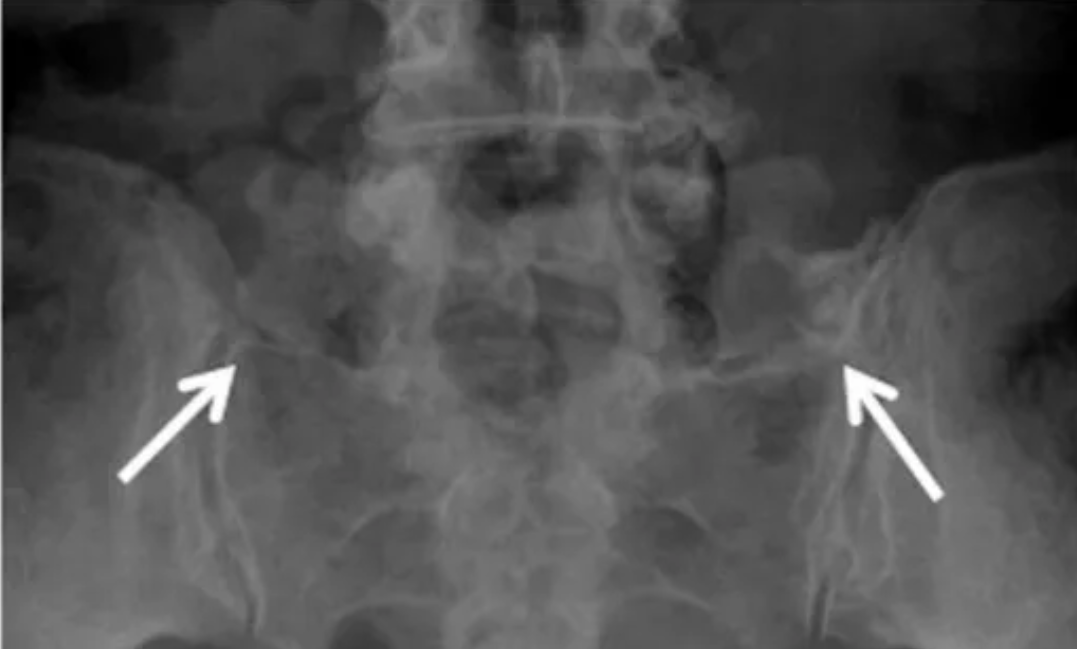

IV型:右侧LSTV II型(长箭头),左侧为III型(短箭头)

(白箭指向假关节,但很难清晰显示)